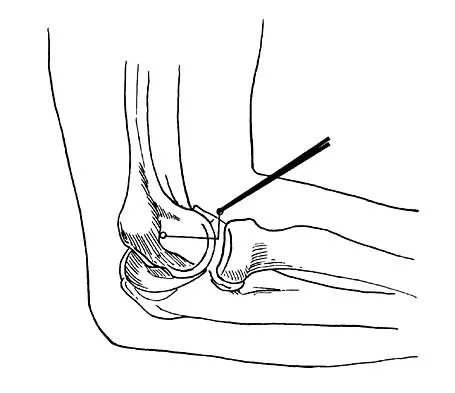

Question 3

A 24-year-old woman fell from a horse and landed on her outstretched right arm. Radiographs reveal an elbow dislocation with a type II coronoid fracture and a nonreconstructable comminuted radial head fracture. What is the most appropriate management?

Explanation